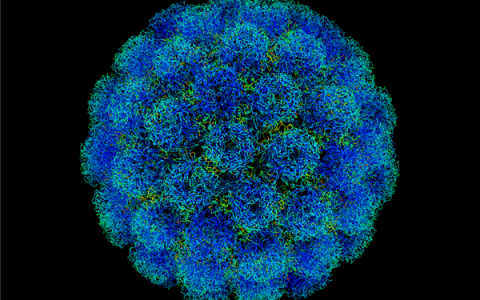

2024年2月,国家癌症中心赫捷院士团队在《国家癌症中心杂志》上发表了一篇题为《2022年中国癌症发病率和死亡率》(CancerincidenceandmortalityinChina,2022)的论文,揭示了中国癌症的相关数据。

研究指出 -